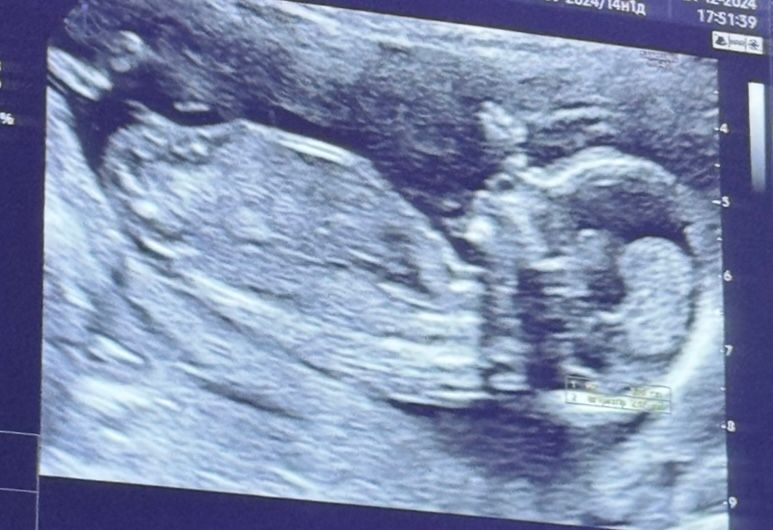

Пол 🩷🩵 На кого похоже?

Изображение

На прошлой неделе писала о том, что на первом скрининге не нашли носовую кость. Сегодня переделала узи платно и слава Богу по узи все хорошо, носовая косточка есть и соответ